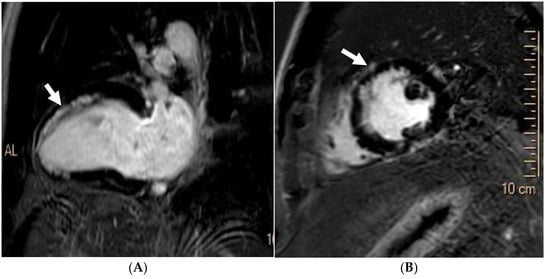

The cardiac MRI acquisition should include standard long-axis and short-axis cine stacks, phase-contrast sequences of the aortic and pulmonary root, and post-contrast sequences [105,106]. These sequences provide a comprehensive morpho-functional evaluation of the mitral valve and subvalvular apparatus, including localising prolapsing segment/s, prolapse severity, leaflet thickness, papillary muscle anatomy, and MAD and MR quantification. CMR has been found to be more sensitive to identifying MAD compared to transoesophageal echocardiography and transthoracic echocardiography [107]. Additionally, cardiac MRI aids in identifying anterior MVP, as it directly correlates with non-ischaemic fibrosis of the papillary muscles and LV inferolateral basal segment (Figure 9). Both of these are linked to prolapsed leaflets and annulus hypermobility [108]. In cases of minimal MR, cardiac MRI may reveal a disproportionate LV remodelling and fibrosis associated with malignant arrhythmias, facilitating the identification of athletes at elevated risk [104]. Further, there is emerging evidence of the role of cardiac MRI in identifying myocardial ECV through T1 mapping. Studies have demonstrated that ECV is increased in MVP patients with MAD compared to those without MAD and MR or isolated MVP [108]. Moreover, MVP patients who have sustained out-of-hospital cardiac arrest exhibit a higher ECV and LGE [30].

Figure 9. A 42 year old Caucasian male, engaging in power sport (recreational) for 20 years, presented with a profound drop in exercise tolerance. Murmur heard on physical examination. T-wave inversion in the inferior leads noted. Supraventricular arrhythmias during an exercise test. Mitral valve (MV) prolapse with moderate regurgitation noted on echocardiogram. Cardiac MRI showed a dilated LV, an LV ejection fraction of 58%, and mitral annular disjunction (arrow) (A). There was prolapse of the posterior MV leaflet with moderate regurgitation (B). Post-contrast imaging identified a subepicardial scar in the lateral wall (arrow) (C,D), consistent with a diagnosis of malignant MV prolapse. He was subsequently referred for MV surgery.